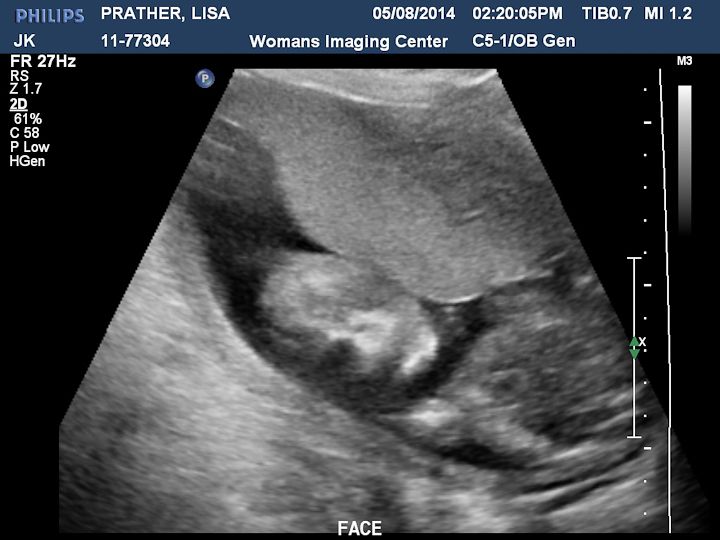

Here are some pictures we got. There is a description on each picture of what you are looking at.

This is a 3D shot of the face.